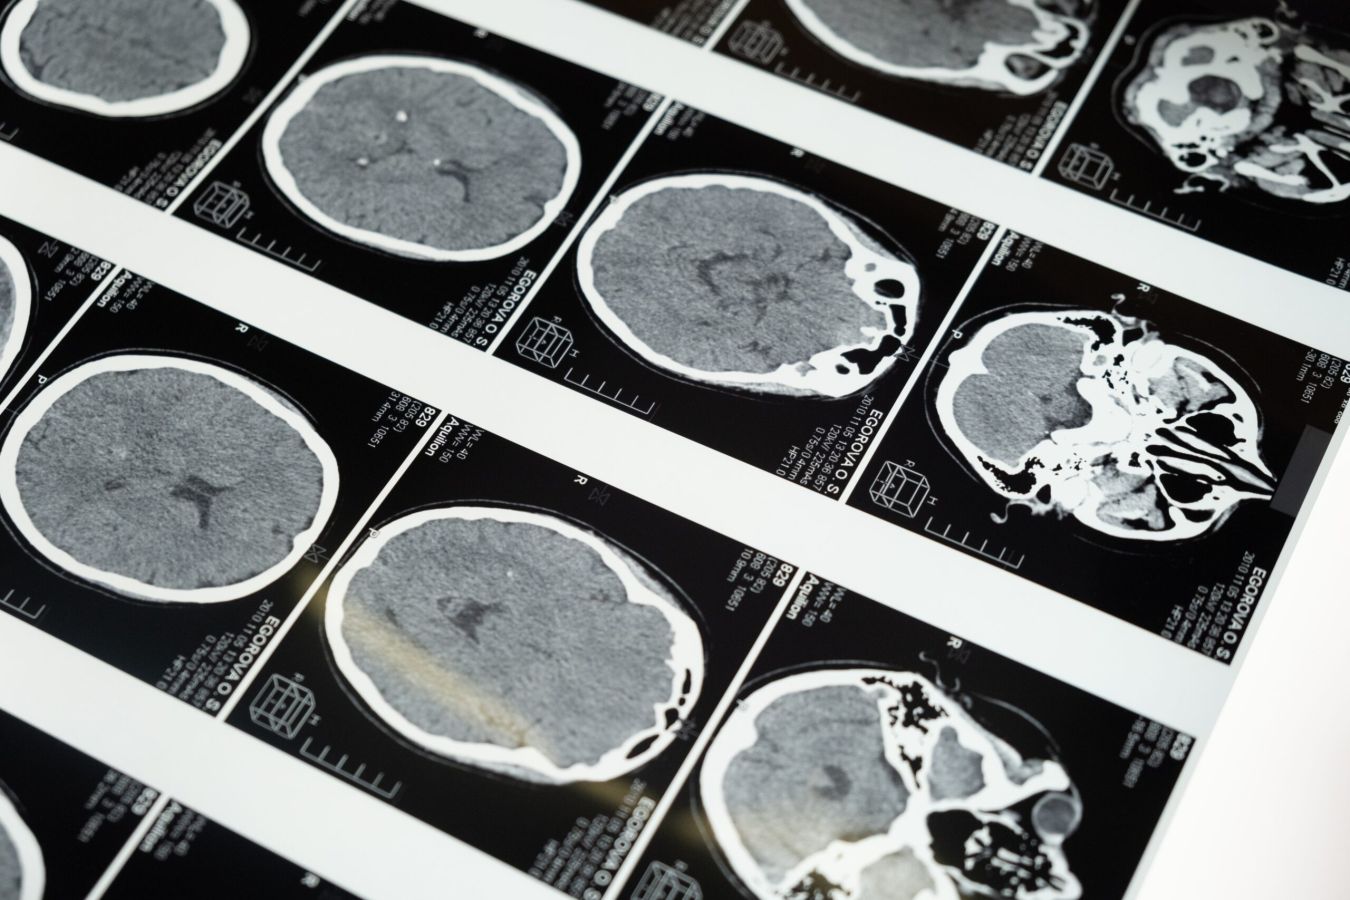

We organiseren een informatiebijeenkomst over omgaan met gevolgen van een herseninfarct, hersenbloeding, TIA, ongeluk met hoofdletsel of hersenoperatie. Tevens gelegenheid tot lotgenotencontact en het stellen van vragen.

Het thema is deze keer: Depressieve gevoelens bij NAH. Sanne Pelser (neuropsycholoog, Basalt) gaat in op dit onderwerp en zal uw vragen beantwoorden. Ad van Dongen, (ervaringsdeskundige) zal ook aanwezig zijn. Het is voor mensen die een herseninfarct, hersenbloeding, TIA, ongeluk met hoofdletsel of hersenoperatie hebben (gehad). Recent of langer geleden. Ook mensen met MS/Parkinson, familieleden en andere geïnteresseerden zijn welkom. Het is op dinsdag 31 mei om 19.00-20.00 uur digitaal via ZOOM.